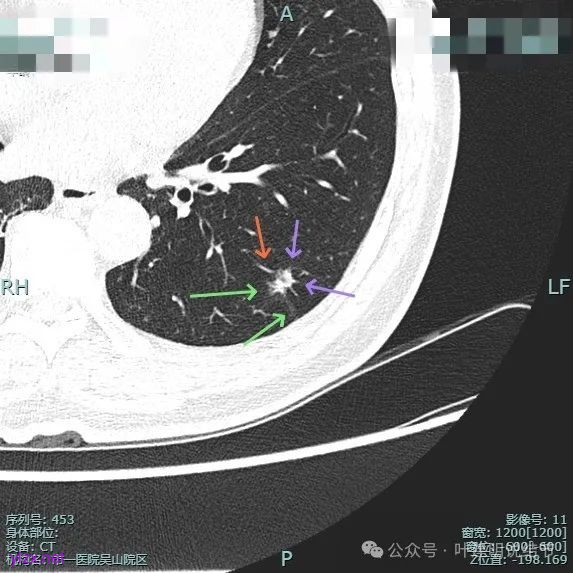

病灶毛刺空泡(或细支气管扩张)都有,表面不平,灶内杂乱。

但纵向看是偏条状些的,密度较高,边上有少许磨玻璃成分,磨玻璃部分略显模糊。

中间实性部分密度过高,边上的的毛刺显得过长,且不太锐利。

相应支气管有扩张,边上的磨玻璃成分偏糊,界限欠清。

进入的血管没有异常增粗,棘突不太锐利,磨玻璃成分偏糊。

上图倒是血管显得有点异常增粗的,总体膨胀性不强,收缩力不够。